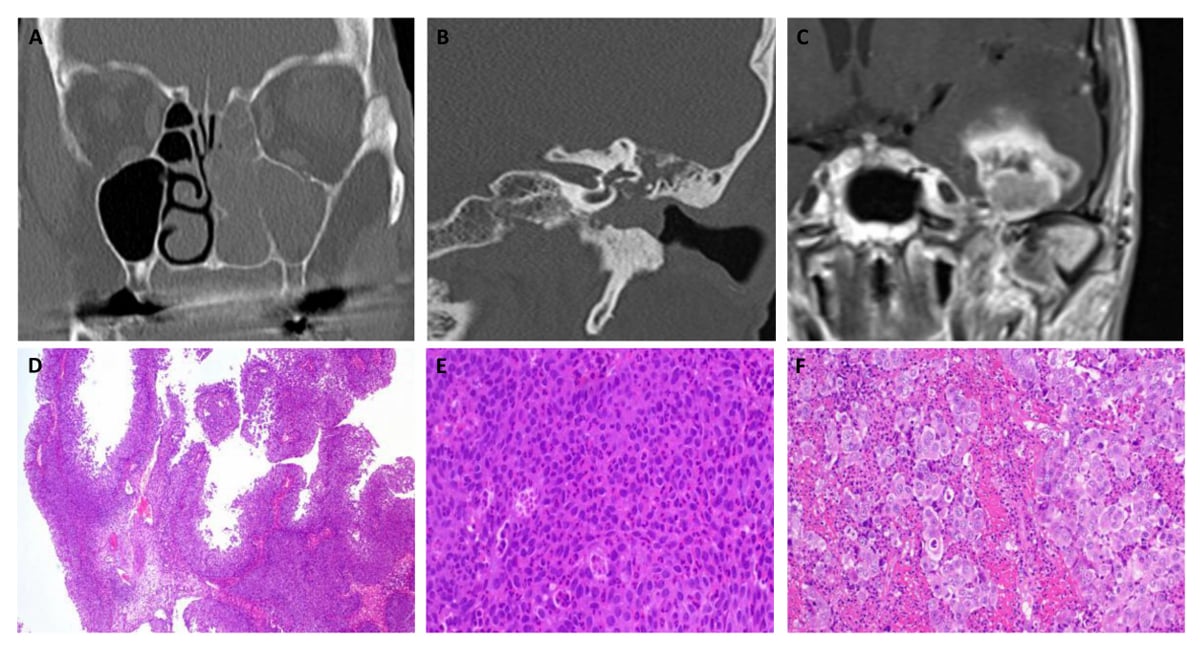

另一名66岁的女性患者的经历则敲响了警钟。她最初同样被诊断为“倒生乳头状瘤”,在经历多次手术后,病情迅速恶化,出现了区域淋巴结转移。尽管后续接受了放化疗,但仍在2019年出现脑转移。此时,通过分子检测才最终确诊为DEK::AFF2融合相关癌。然而,由于发现时已是晚期,患者最终因病情恶化不幸离世。这个案例沉痛地说明了早期精准诊断对于改善此类患者预后的极端重要性。